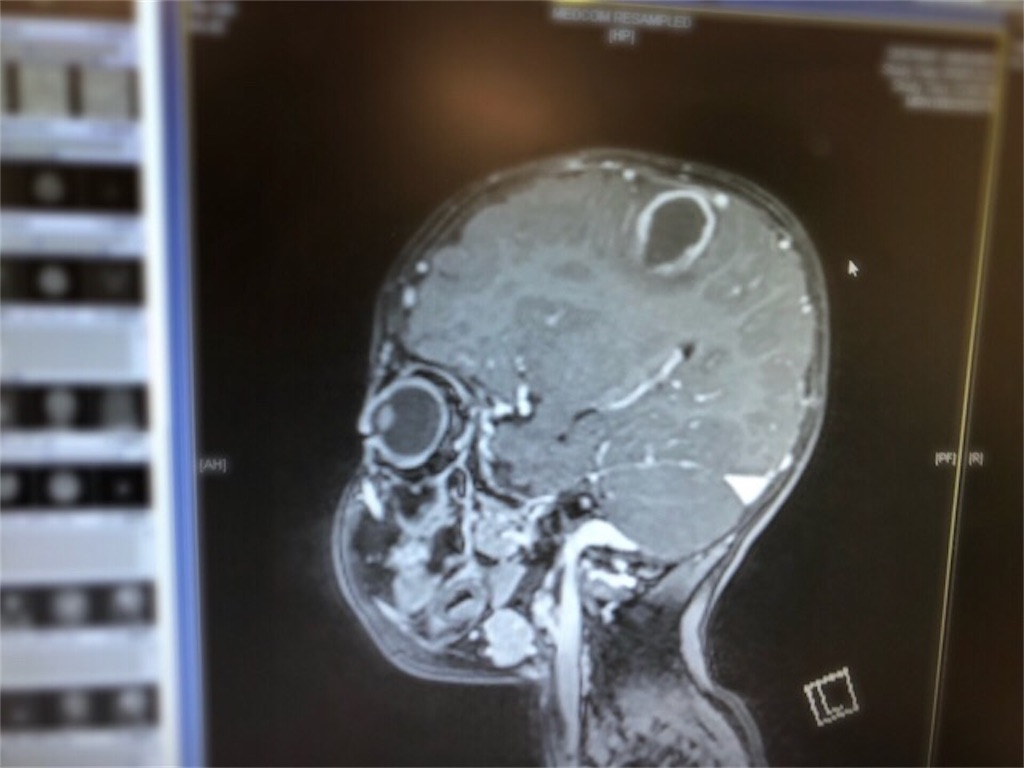

両方向性グレン手術後

術後MRSA(様々な抗生物質に耐性のあるブドウ球菌)に感染して長期間治療していた

フォンタン手術→フォンタンテイクダウン手術

ようやくフォンタン手術に到達したと思ったのに、テイクダウン(フォンタンの前に戻すこと)になり、全身状態も悪化した

肺気腫になり、敗血症になり、胸水が止まらず危険な状態だった